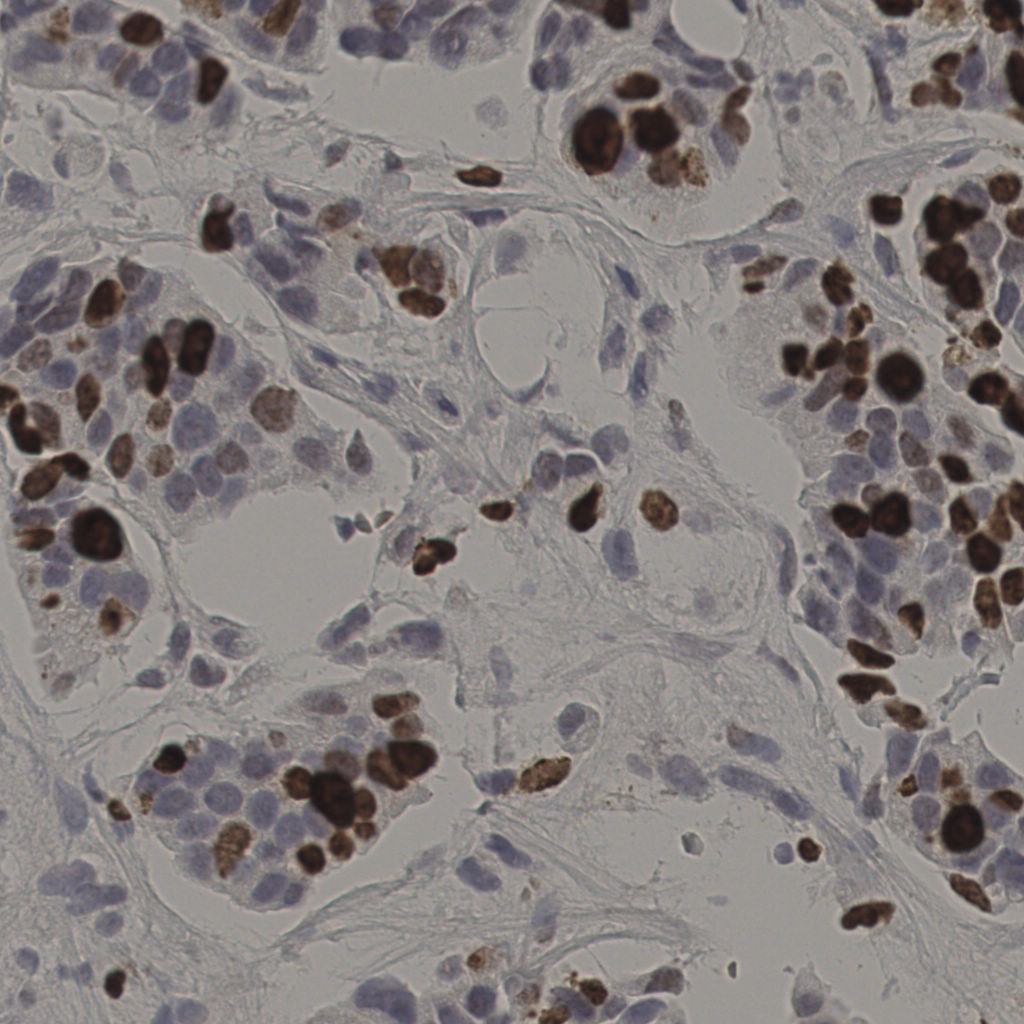

17.75%

Ki67 指数

阴 7986 阳 1723

切片统计

总切片 2640

有效 412

已标记 412

有效率 16%